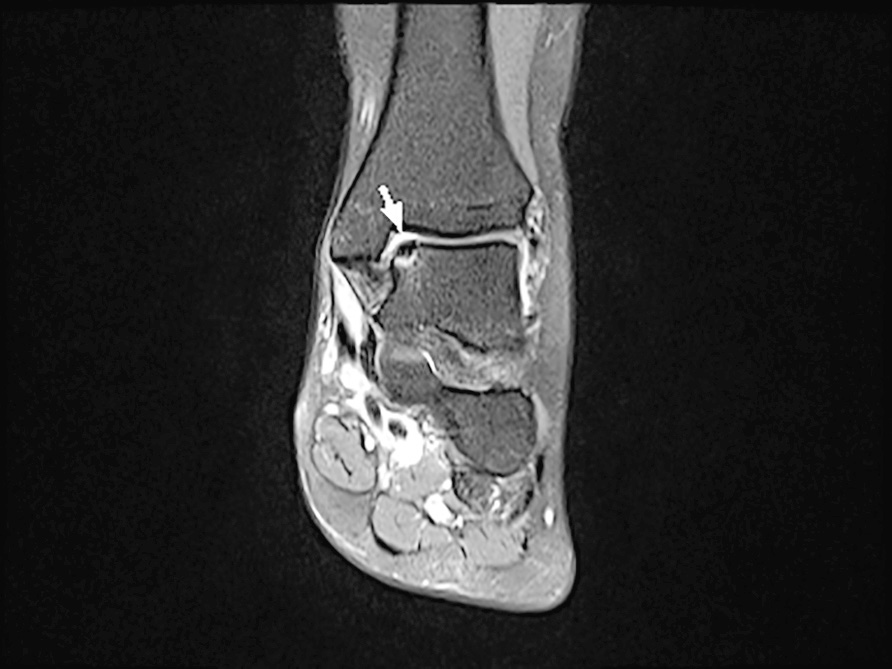

- Classificazione di Hepple 6, basata su immagini RM. Prevede 5 stadi:

- stadio III e IV indicano gradi crescenti di separazione del frammento OC (Fig. 1);

- stadio V: cisti subcondrale con cartilagine sovrastante integra.